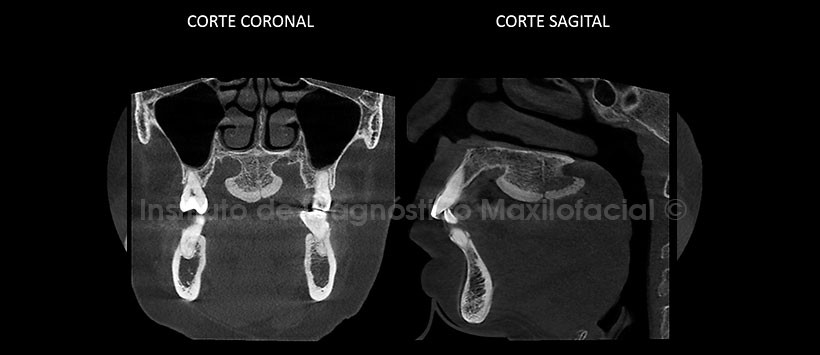

A la evaluación de la tomografía computarizada de haz cónico (CBCT), mediante cortes axiales (Figura1), cortes coronal y sagital (Figura 2), se evidencia la presencia de una excrecencia ósea de gran tamaño localizada en la parte media del paladar, de forma lobular, aspecto pediculado con una sola base amplia, donde se pueden observar varias capas: una compacta próxima al piso de la fosa nasal, otra esponjosa y finalmente una cortical muy gruesa en la periferia.

Imágenes sugerentes de torus palatino.